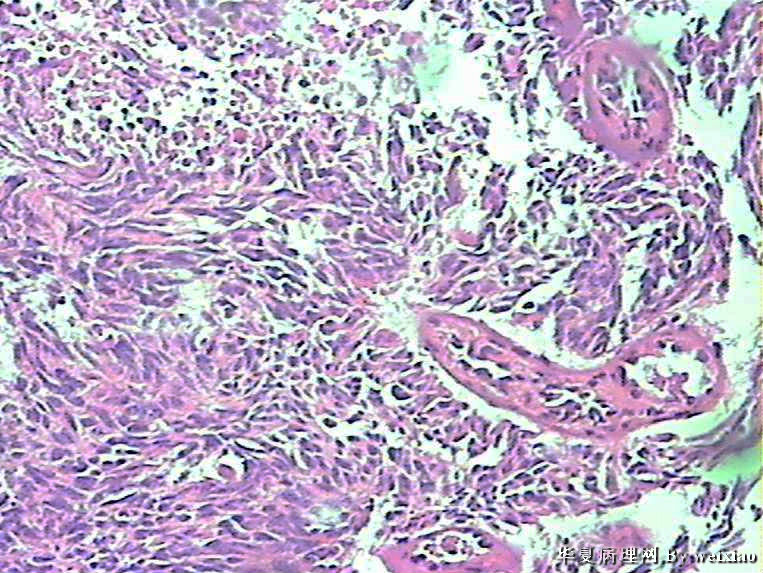

病史:男45岁,头痛2个月,手术所见:额叶占位性病变,与周围正常脑组  织的界限不清。

大体:灰白色碎组织一堆,质软,大小:2.5*1.8*1.3cm

• 额叶肿瘤图2

图2

×参考诊断

胶质母细胞瘤

会诊胶质母细胞瘤

The tumor cells are kind of spindle, need to rule out gliosarcoma, you need to check MRI films, do immunostain for GFAP, and vimentin. The vascular proliferation (VP) supports GBM.

肿瘤细胞呈梭形,血管增生明显,有坏死,符合胶质母。